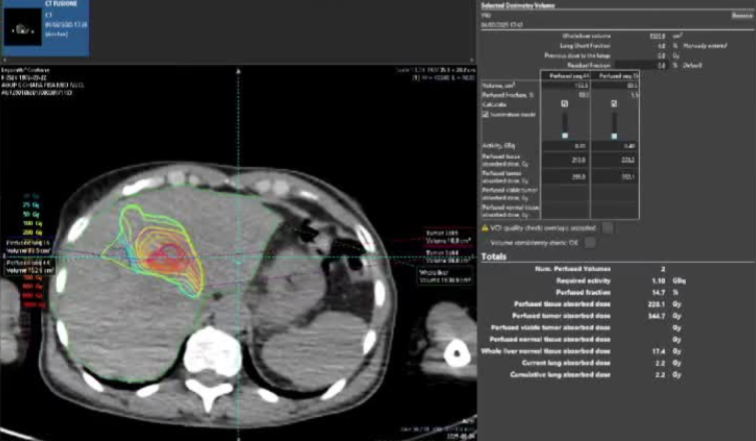

· 单中心、样本量小; 83 岁的女性,体重超标 40 毫米单发 ICC(S7-S8) 中肝静脉和右肝静脉浸润性,活检:非酒精性脂肪性肝炎(慢性肝病),马斯氏(MaS)病(30%)

考虑采用“三步策略 TARE→ PVE → Surgery”方案 剂量活性:1.56 和 3.16 GBq